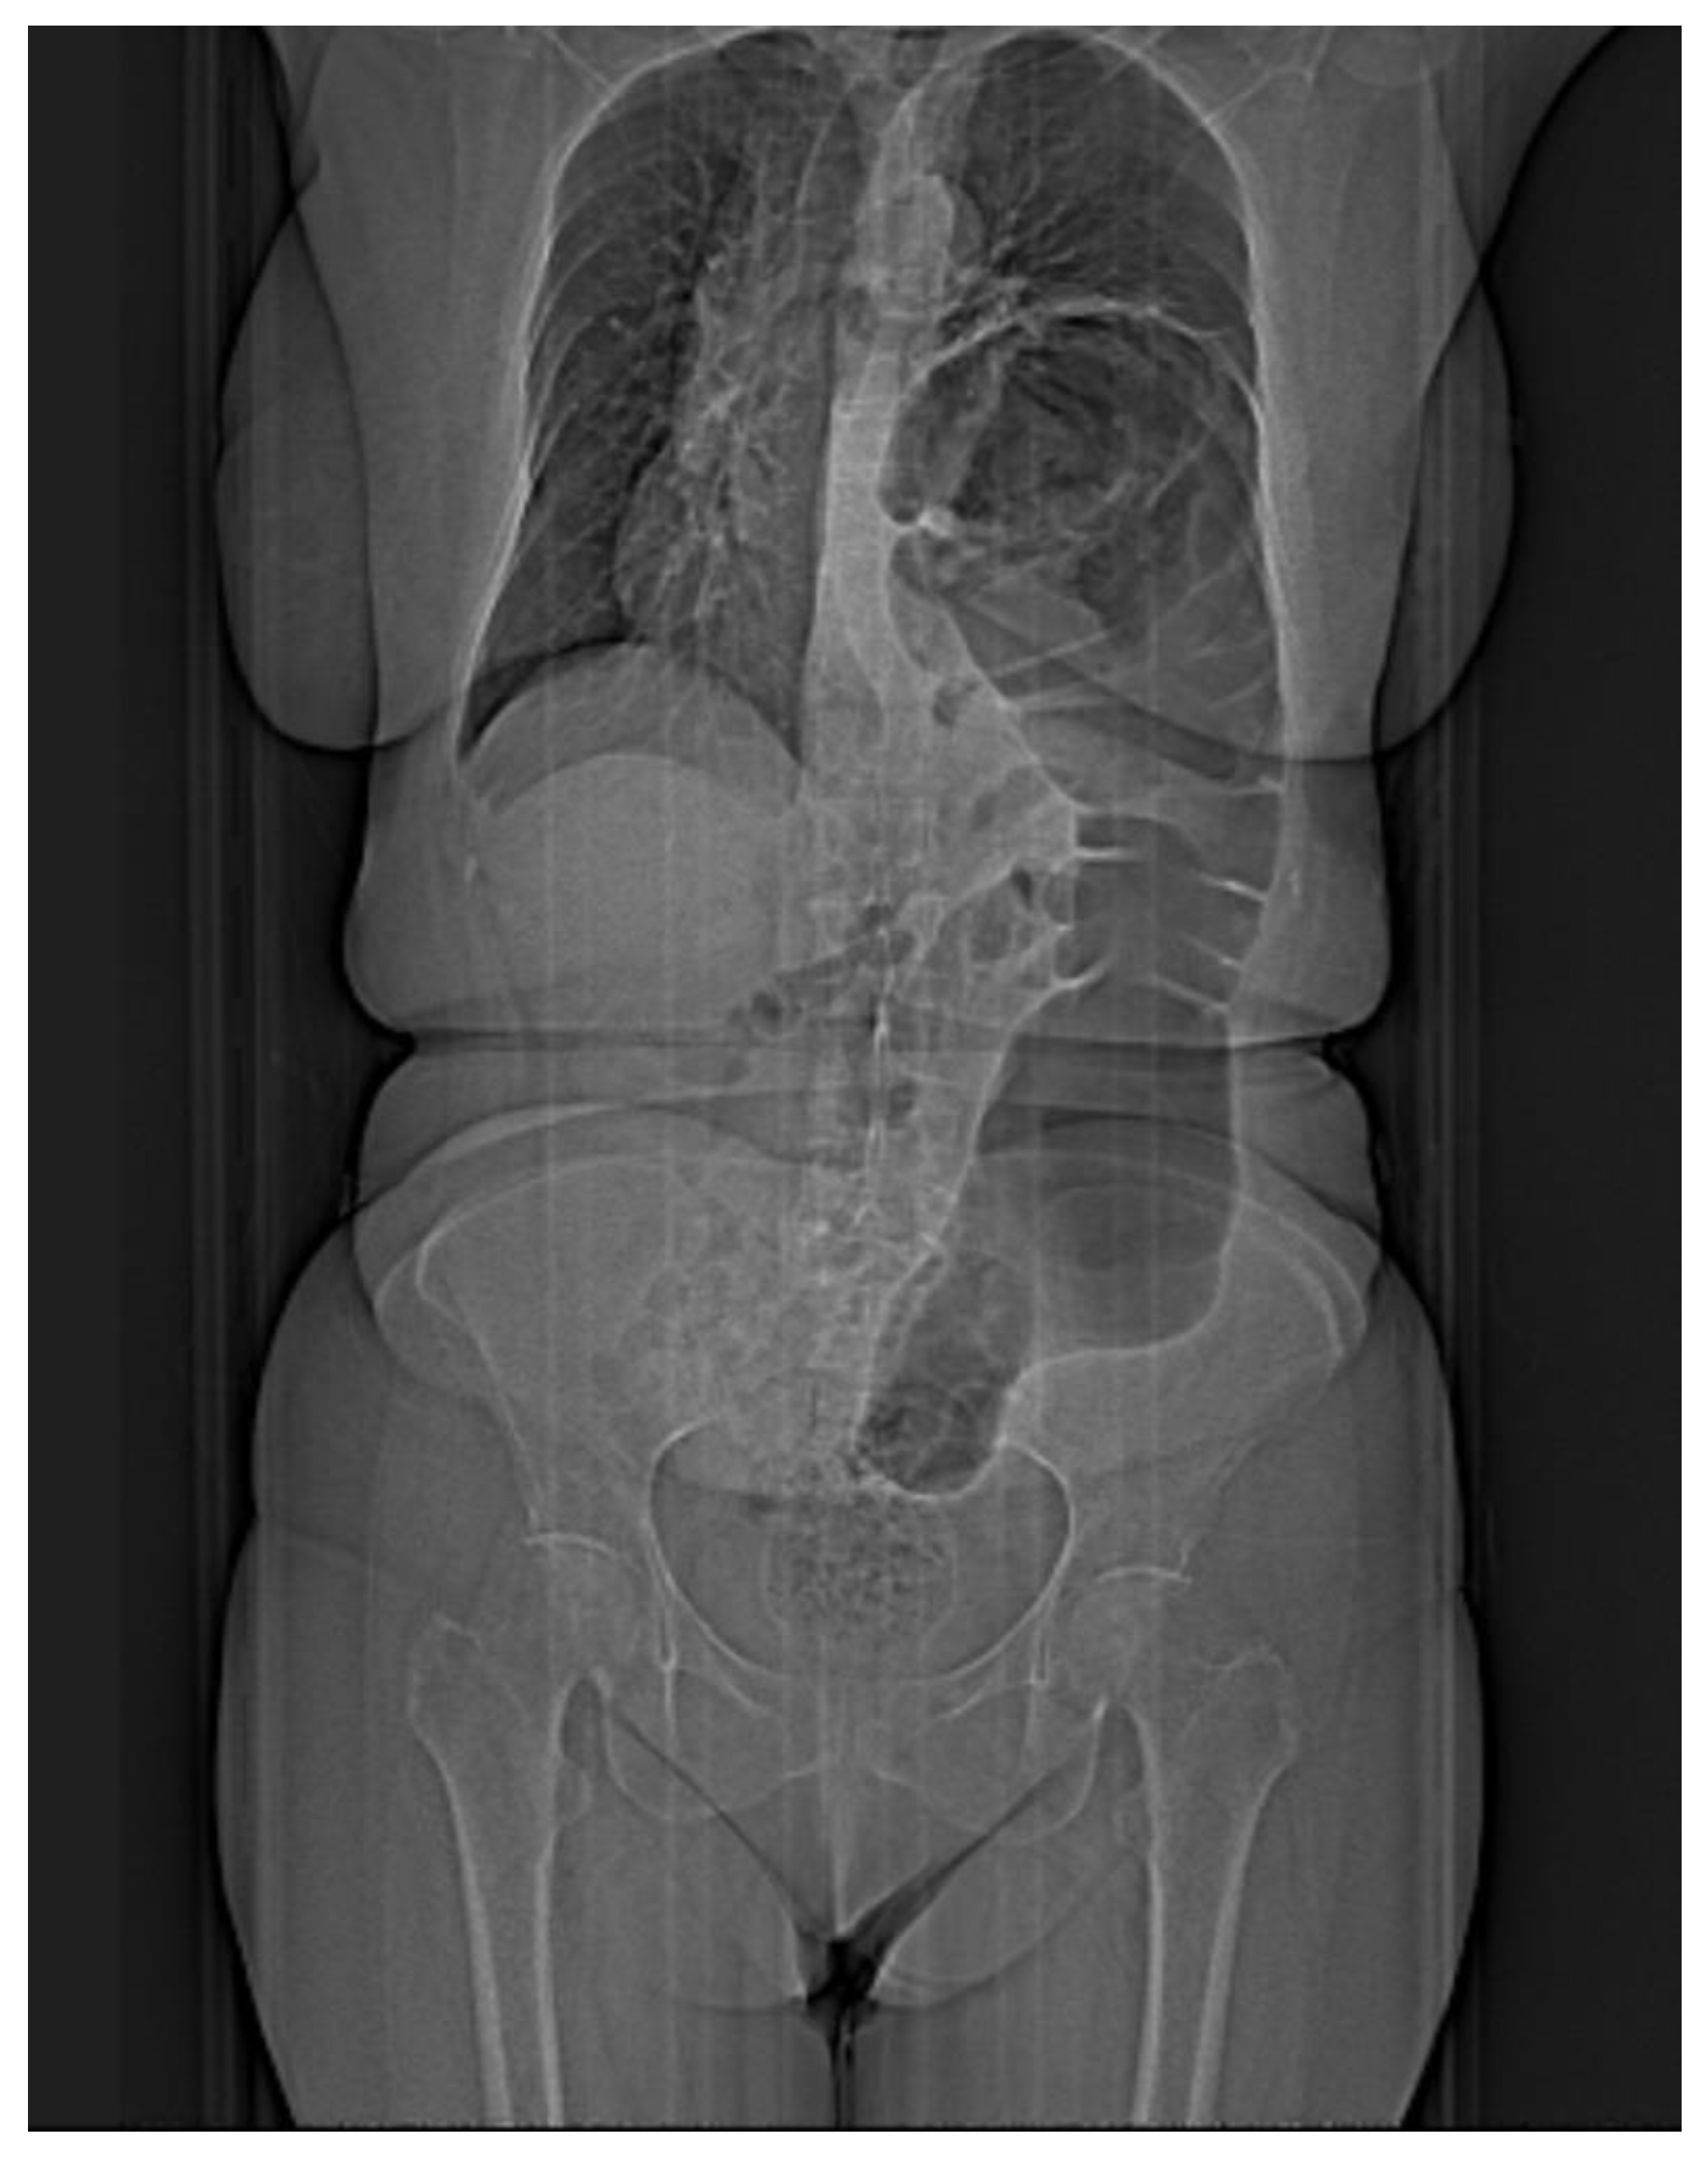

Computed tomography refines the diagnosis by accurately identifying the location, dimensions of the defect, the hernial sac, and the intrathoracic herniation of viscera [17] (Figure 3A–C). Tomographic imaging represents a key element in establishing therapeutic decisions. CT has a sensitivity for left-sided injuries that is greater (78–100%) than for right-sided injuries (50–79%). The presence of a pleural effusion, a pulmonary atelectasis, simultaneously with the identification of digestive viscera at the thoracic level is revealing for diagnosis.

Figure 3. CT thorax with contrast. Frontal (A), sagittal (B), and transverse (C) section showing large diaphragmatic defect (Bochdalek hernia) with intrathoracic herniation of the colon.